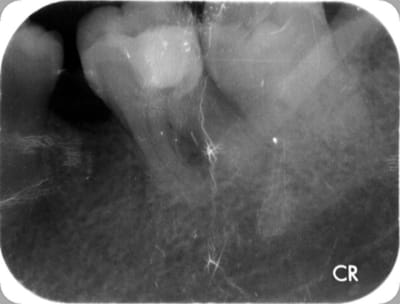

Ben alors j'ai un cas là justement : je fais quoi? Onlay ou Couronne?

Dent vivante, CVI renforcé après la taille en coiffage attente de 3 semaines avec pansement pour être sûr, RAS dent toujours vivante quand je l'ai revu aujourd'hui.

Aujourd'hui : retouche du CVI puis (première photo au stade du mordançage) compo pour le core build-up, pansement.

Les photos sont pas top mais pour le moment je fais avec ce que j'avais sous la main...

Qu'est-ce que je fais pour la suite du coup? Onlay ou Couronne?

PS. On ne voit pas bien la différence à la radio avant-après... Désolé.

Perso je penche pour la couronne...